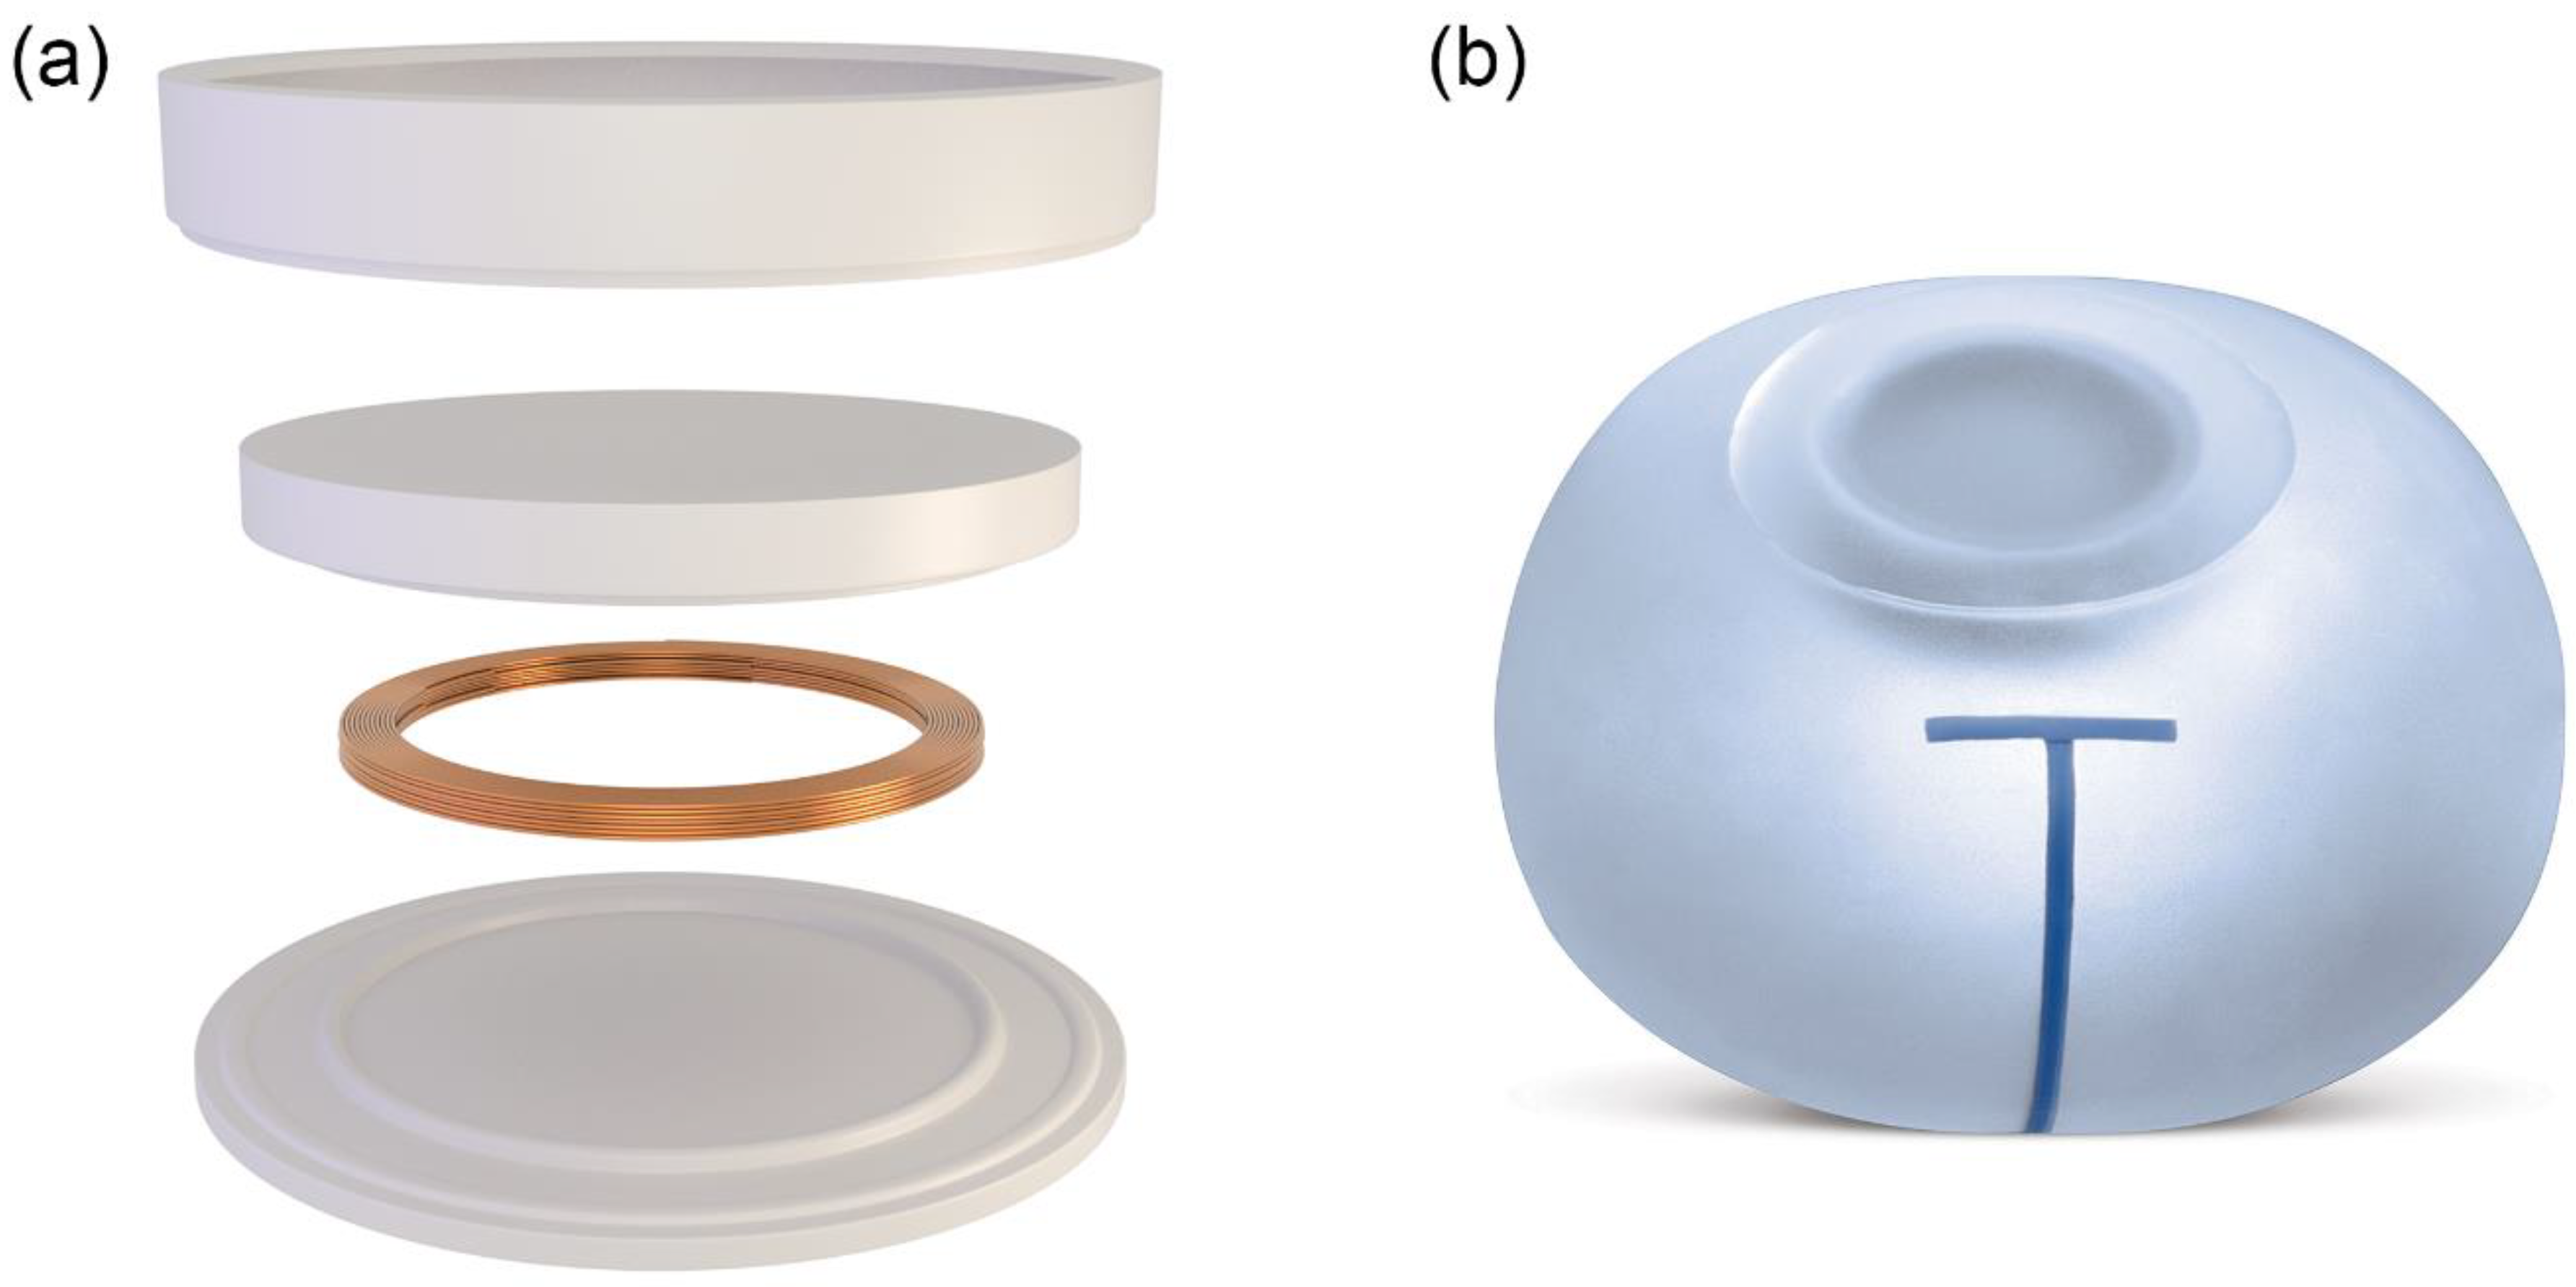

2.1. Tissue Expander

| Parameter | Traditional Expander | Motiva Flora® |

|---|---|---|

| Identification of port location | Magnet | RFID coil |

| Material | Neodymium | Copper |

| Density | 7.01 g/cm3 | 8.96 g/cm3 |

| Diameter | 13.3 mm * | Outer: 24.7 mm Inner: 20.3 ± 0.2 mm |

| Height | 4.4 mm * | 2.150 ± 0.1 mm |

| Needle guide | ||

| Material | Stainless steel | Polyetheretherketone |

| Density | 7.5~8 g/cm3 | 1.3 g/cm3 |

| Diameter | 36.5 mm * | Dome: 40.1 mm *, Needle stop: 26.8 mm * Base: 42.5 mm * |

| Height | 10.0 mm * | 12.9 mm * |

| Thickness | 2.1 mm * | 1.5 mm * |